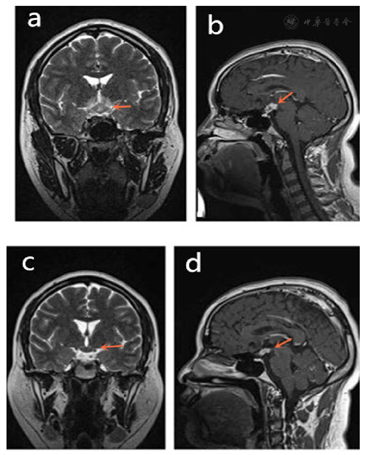

为进一步诊治,将患者收治入院。考虑到LCH多为多器官累及,完善了相关检查。甲状腺实验室检查:T3 1.33ug/L,T4 34.40 ug/L,FT3 4.46 pmol/L,FT4 5.62 pmol/L,ATG-Ab 161.2 kU/L,TPO-Ab 40.8 kU/L;24小时尿量7600 ml,尿比重(折射仪法):1.0027;颅脑MRI平扫提示鞍上池病变(鞍上池区见结节状异常信号灶,呈稍长T1稍长T2信号,边界欠清,大小约2.3 cm×1.6 cm);腹部CT示肝胃间隙、后腹膜多发淋巴结肿大。

治疗采用化学疗法,方案VP,即:长春新碱4 mg,每周一次,连续6周,泼尼松40 mg bid口服,连续28 d。疗程结束后复查,累及部位病灶均较前缩小。